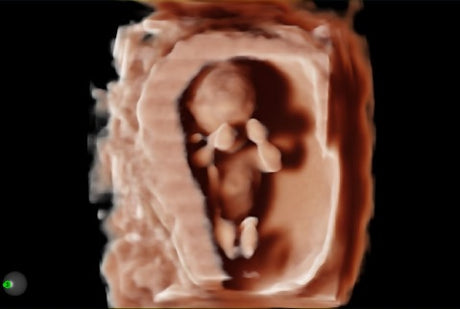

Les échographes Esaote offrent une restitution d’image d’une grande précision, permettant un diagnostic fiable dans toutes les spécialités. Le traitement numérique optimise le contraste et la netteté, réduisant les artefacts et améliorant la détection des tissus pathologiques. Ces performances sont particulièrement appréciées en gynécologie, où la lisibilité des structures pelviennes ou obstétricales est déterminante.

Un gynécologue privilégiera un échographe offrant une résolution d’image très fine et une compatibilité avec des sondes endocavitaires. Un kinésithérapeute ou un médecin du sport recherchera plutôt un appareil portable, léger et rapide à mettre en route. Les praticiens généralistes apprécieront la polyvalence et la facilité d’entretien, tandis que les vétérinaires auront besoin d’un système robuste et facilement transportable.